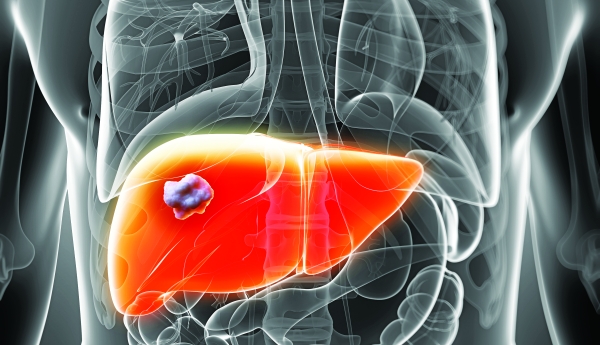

Ενα βήμα πιο κοντά στη χρήση οργάνων που αναπτύσσονται από «βιοεκτυπωτές» βρίσκονται επιστήμονες στις ΗΠΑ, οι οποίοι έχουν αναπτύξει το πρώτο τρισδιάστατο συκώτι και ετοιμάζονται να το διαθέσουν σε μερικούς μήνες για τοξικολογικές έρευνες που διεξάγονται από φαρμακευτικές εταιρίες.

Το τεχνητό συκώτι δημιούργησαν πριν από μερικούς μήνες επιστήμονες της εταιρίας βιοτεχνολογίας Organovo, η οποία δημιουργεί λειτουργικό τρισδιάστατο ανθρώπινο ιστό που χρησιμοποιείται για ιατρικές έρευνες και θεραπευτικές εφαρμογές.

Οι επιστήμονες παρουσίασαν πρόσφατα τη μελέτη τους σε συνέδριο που πραγματοποιήθηκε στο Σαν Ντιέγκο, όπου δήλωσαν ότι η πρώτη διάθεση του τεχνητού ήπατος για τη διεξαγωγή τοξικολογικών ερευνών θα γίνει εντός του 2014.

Οπως εξήγησαν στην παρουσίασή τους, όταν τα φάρμακα ελέγχονται για την τοξικότητα ή την αποτελεσματικότητά τους, χρησιμοποιούνται κυρίως κύτταρα από το συκώτι και κυρίως παρεγχυματικά ηπατοκύτταρα, τα οποία όταν βρίσκονται στον οργανισμό παρουσιάζουν εξαιρετική ικανότητα πολλαπλασιασμού. Ετσι, ακόμη και όταν αφαιρείται χειρουργικά έως και το 70% από αυτά, εκείνα που απομένουν στο συκώτι είναι αρκετά για να το βοηθήσουν να αναγεννηθεί και να αποκατασταθεί η αρχική ηπατική μάζα.

Ωστόσο, όταν αφαιρούνται από το σώμα, τα κύτταρα αυτά χάνουν γρήγορα την παραπάνω ικανότητα και πραγματοποιούν μόνο τις πολύ βασικές λειτουργίες, οι οποίες εξαρτώνται εν μέρει από την «αρχιτεκτονική» του οργάνου, δηλαδή το ακριβές μοτίβο ή τα επαναλαμβανόμενα μοτίβα που δημιουργούνται από τους πολλούς και διαφορετικούς κυτταρικούς τύπους που υπάρχουν στο εσωτερικό οποιουδήποτε ιστού.

Σύμφωνα με τους επιστήμονες, σ’ αυτό ακριβώς το σημείο μπαίνει στο παιχνίδι η «βιοεκτύπωση», η οποία αναπαράγει τα απαραίτητα «αρχιτεκτονικά» χαρακτηριστικά του πραγματικού ανθρώπινου ιστού, όταν υπάρχει έστω ένα πρωτότυπο. Αυτό επιτυγχάνεται επειδή τα κύτταρα του ήπατος διατηρούν τις βασικές λειτουργίες τους και έξω από το σώμα, για διάστημα πολλών ωρών.

Οι επιστήμονες δήλωσαν ότι, παρόλο που η χρήση των τεχνητών οργάνων στον άνθρωπο απέχει αρκετά χρόνια ακόμα, η μέθοδος «βιοεκτύπωσης» αποτελεί ένα πολύ σημαντικό βήμα προς αυτήν την κατεύθυνση.